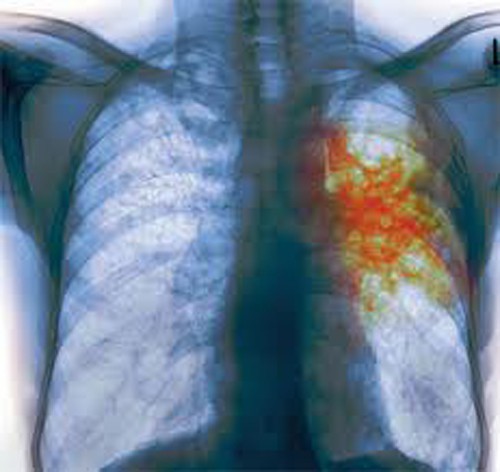

Туберкулез легких – инфекционный процесс развивается непосредственно в легких человека. Данная форма является наиболее распространенной в современном обществе, поскольку возбудители легко передаются здоровым людям воздушно-капельным путем. Отметим также, что с током крови и лимфы палочки могут проникать в другие органы и системы.

Поскольку наиболее распространенной на сегодняшний день формой инфекции является туберкулез легких (диагностируется в 60-70% случаев), мы подробно рассмотрим симптомы туберкулеза именно этой разновидности, тем более что они характерны и для других типов болезни. Итак, у больных наблюдаются следующие признаки туберкулеза:

Специфическая профилактика туберкулеза основывается на вакцинации населения и регулярных флюорографических обследованиях. Последние позволяют вовремя выявить туберкулез легких и начать лечение на ранних стадиях, что снижает вероятность летального исхода. Более частые обследования применяются в отношении лиц, постоянно контактирующих с больными людьми.